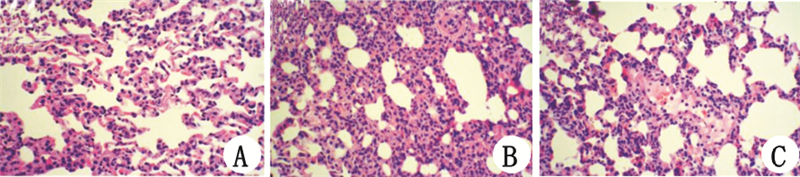

2 结果 2.1 各组大鼠肺损伤的比较假手术组大鼠肺大体观察呈粉红色,光镜下肺泡结构完整,肺泡腔清晰,肺间质无水肿,无白细胞浸润(图 1A);脓毒症组大鼠大体观察肺表面暗红,包膜下点、片状出血,切面有黄色液体,光镜下肺泡结构不清晰,肺泡隔增宽,透明膜形成,肺泡内见白细胞渗出、出血,肺间质见大量炎症细胞浸润(图 1B);MRP4抑制剂干预组较脓毒症组肺组织破坏和炎性细胞浸润显著减少(图 1C)。

|

| A、B、C分别为假手术组、脓毒症组和MRP4抑制剂干预组 图 1 肺组织病理切片HE染色的代表性图片(×200) Fig 1 Representative optical microscopy images of lung tissue sections in the three groups(×200) |